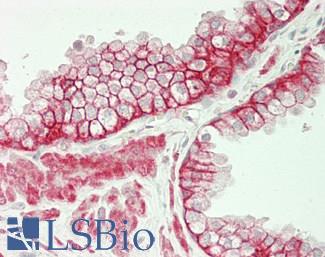

Anti-CDH17 / LI Cadherin antibody IHC of human small intestine. Immunohistochemistry of formalin-fixed, paraffin-embedded tissue after heat-induced antigen retrieval. Antibody LS-B6022 concentration 5 ug/ml.

CDH17